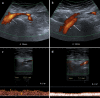

Fig. 18

Transverse sub-xiphoid Ultrasonographic scan. a Color Doppler US performed in inspiratory apnea that shows a regular diameter of the CA (short arrow). Epatic artery (long arrow). Splenic artery (head of arrow). b Color Doppler US performed in expiratory apnea that shows severe stenosis at the origin of the CA with aliasing due to turbulent flow and high-speed peak. c Duplex Doppler US of the CA performed in inspiratory apnea that shows a slight increase in peak speed. d Duplex Doppler of the CA performed in expiratory apnea that shows very high peak speeds (> 200 cm/s) due to severe stenosis